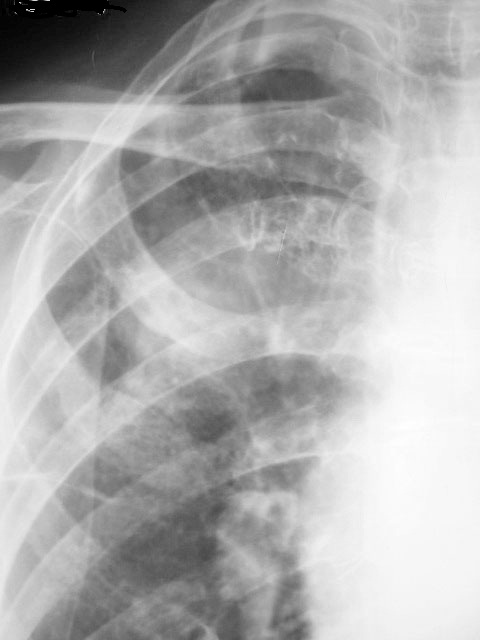

以下是引用随光逐影在2010-4-4 17:47:00的发言:[br]右上肺肿块,不排除肿瘤性病变;建议行ct扫描检查。

以下是引用zxl51642在2010-4-4 15:11:00的发言:[br]做ct看看.